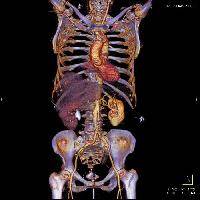

Магнитно-резонансная томография (МРТ):один из самых эффективных методов диагностики заболеваний